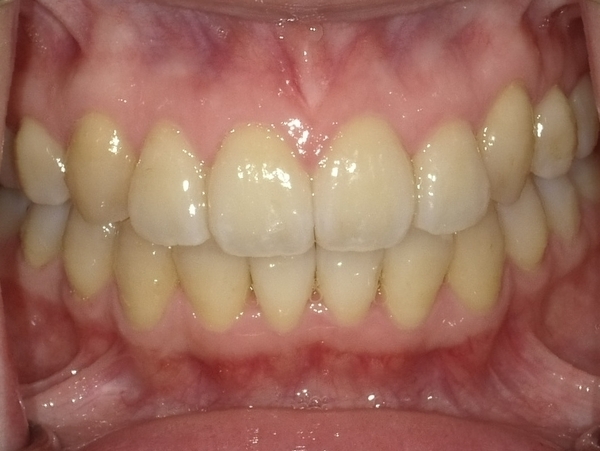

ガタガタとした歯並びや八重歯(叢生)CASE68